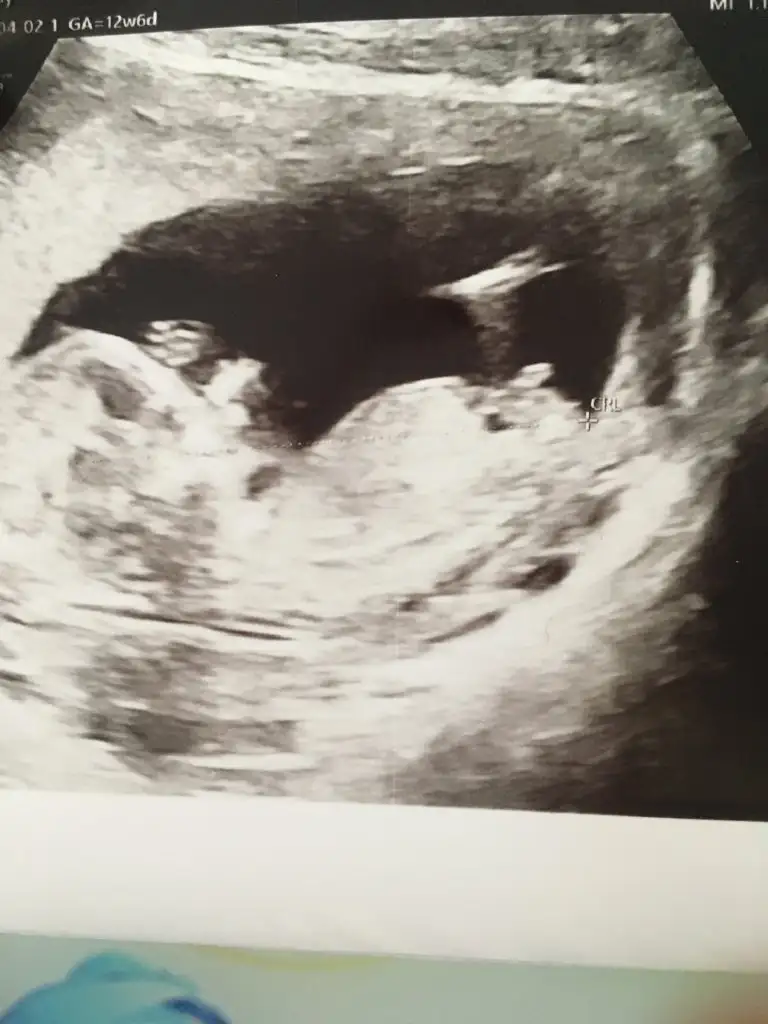

dr soylemeden siz gorun genital nub teorisi ( bebegin cinsiyeti)

Arkadaşlar lutfen tahmin eder misiniz

Kızlar benim nub teorisi tuttu kızım olacak inşallah 🤗 Bu ara isim arayışındayız isim önerileriniz varsa alırım valla 😍